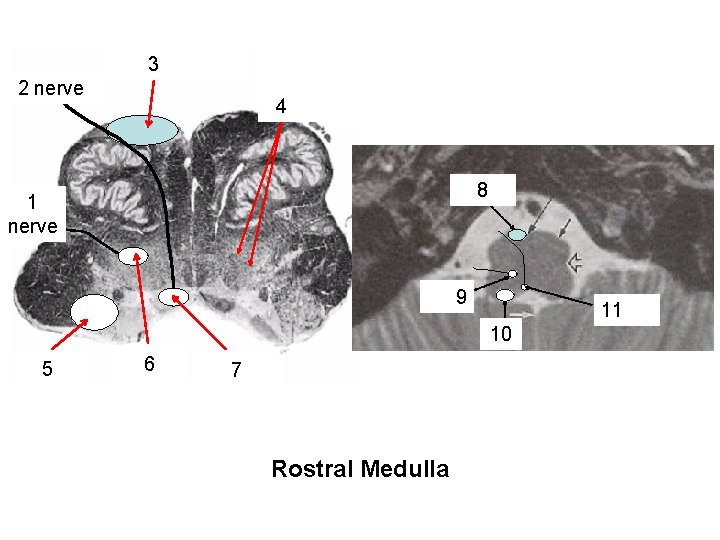

Hypoglossal 2 nerve roots Pyramidal 3 (corticospinal) tract reticular formation with reticular nuclei + & descending rubrospinal & reticulospinal fibers 4 8 pyramidal tract Vagal 1 Nerve nerve roots nuc. ambiguus 9 11 Hypoglossal nuc. Vest. 10 Nuc. vestibular 5 nuclei nucleus hypoglossal 6 7 ambiguus nucleus Rostral Medulla